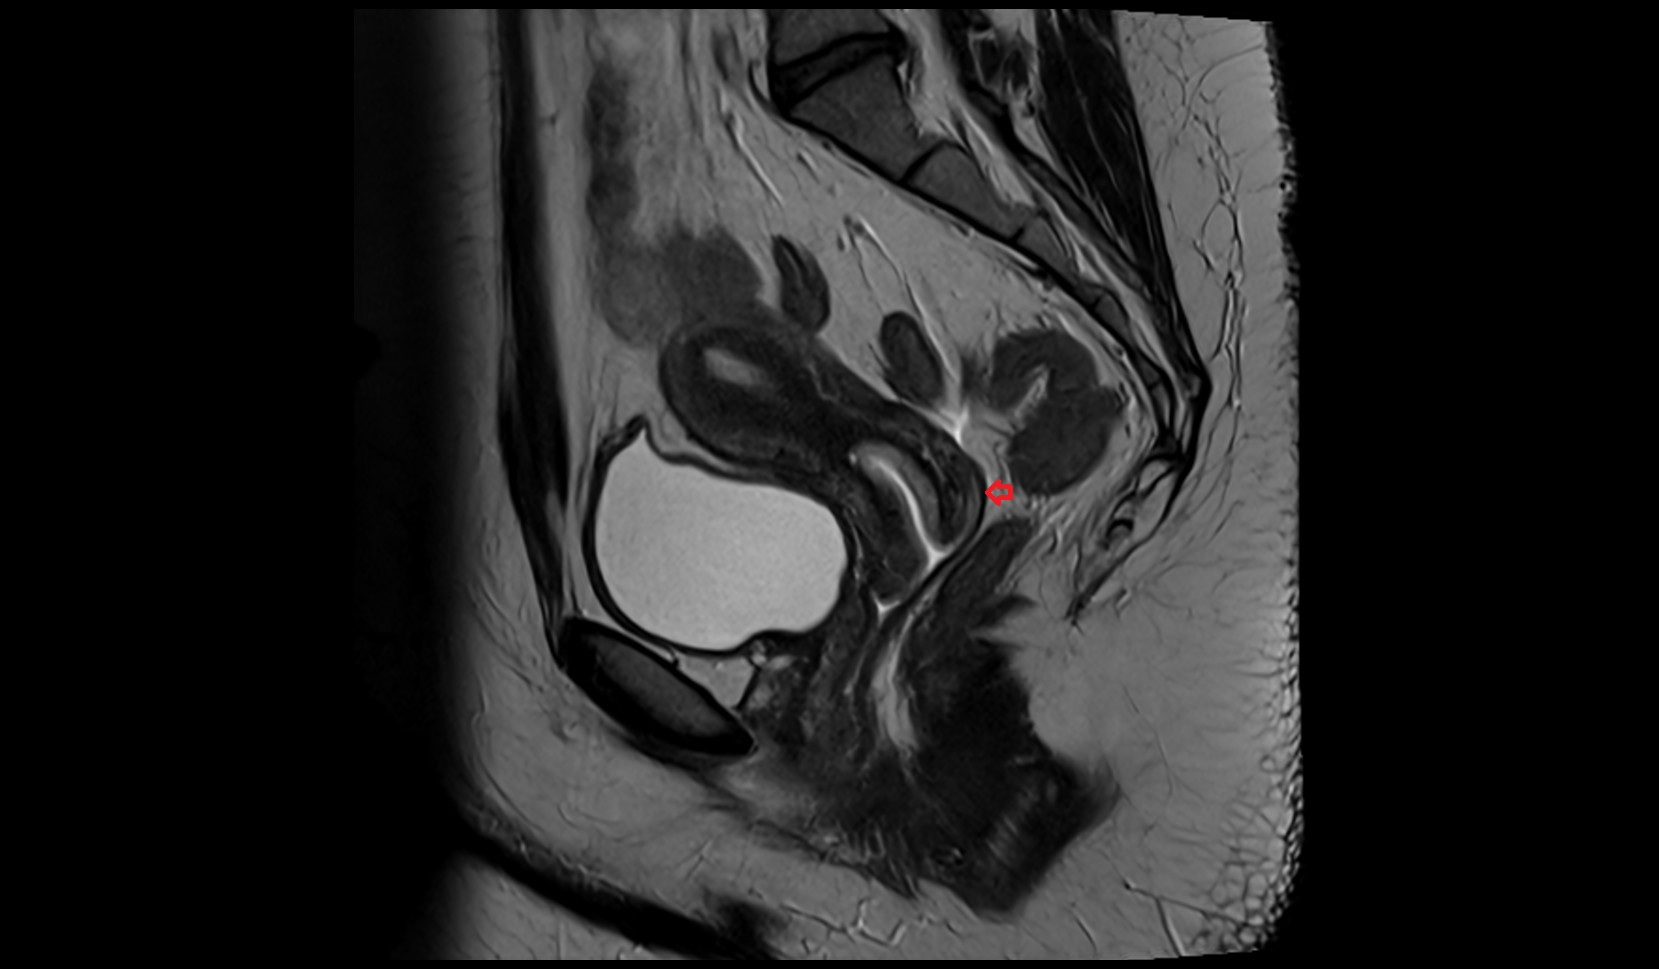

- Uterus

- Body of uterus

- Fundus of uterus

- Cervix of uterus

- Isthmus of uterus

- Vagina

- Fornix of the vagina

- Endometrium of uterus

- Myometrium of uterus

- Perimetrium of uterus

- Junctional zone of uterus